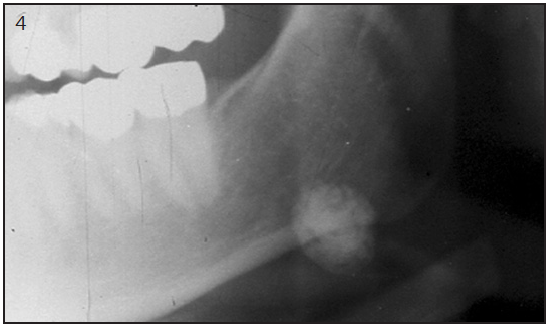

Tumors and structural alterations in the salivary glands can be visualized with sialography, ultrasonography, MRI or CT imaging.25 These techniques are useful to detect. Figure 4 shows a radiograph of a sialolith. These are not functional measures but are useful for diagnosis of salivary dysfunctions.

Figure 4 – Radiograph of a sialolith.

Figure 4